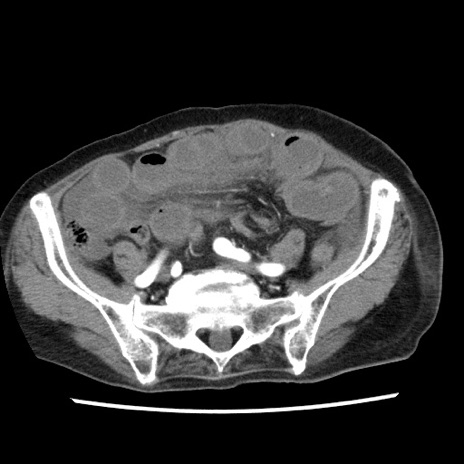

冠状断像

【症例】80歳代女性

【主訴】腹痛

【現病歴】8時間前から腹痛あり来院。

【既往歴】糖尿病、脂質異常症、子宮体癌にて子宮全摘術

【身体所見】意識清明・会話良好だが腹痛で苦悶様、全腹部にわたって反跳痛と圧痛あり

【データ】WBC 13600、CRP 0.14、LDH 224、CK 90